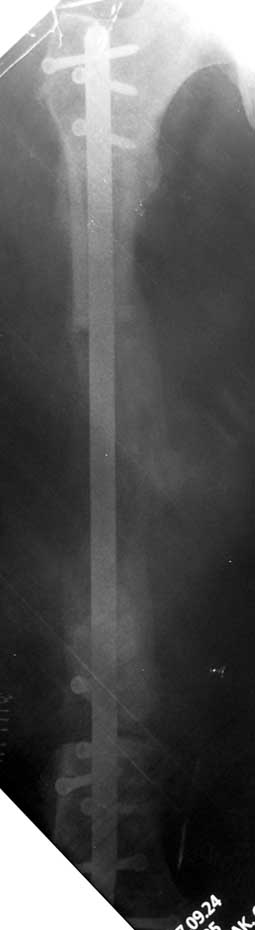

Eksternal fiksatör ile geçen süre (eksternal fiksasyon indeksi), gereken distraksiyon miktarına bağlıdır ve bu süre boyunca bazı komplikasyonlarla karşılaşılabilir. Distraksiyon dönemi sona erdikten sonra, distraksiyon süresinin iki katını aşan konsolidasyon döneminde hastalar eksternal fiksatörü zorlukla tolere edebilirler. Yeterli konsolidasyon sağlanmadan eksternal fiksatör çıkartılırsa ise kırıklar, deformite ve kısalık oluşabilir. Hastanın fiksatör ile birlikte geçirdiği sürenin azaltılması ve böylece hasta konforunun ve aktivite düzeyinin arttırılması için intramedüller çivi üzerinden uzatma yöntemi uygulanmaktadır. Bu yöntemde distraksiyon dönemi sona erdiğinde kemiğin içindeki çivi statik olarak kilitlenmekte ve eksternal fiksatör çıkartılmaktadır. Stabilizasyon intramedüller çivi tarafından sağlandıktan sonra konsolidasyon dönemi gerçekleşmektedir. Bu şekilde hem eksternal fiksatörün uzun süre kalmasından hem de erken çıkartılmasından kaynaklanan komplikasyonların önüne geçilmektedir.

Vaka 1